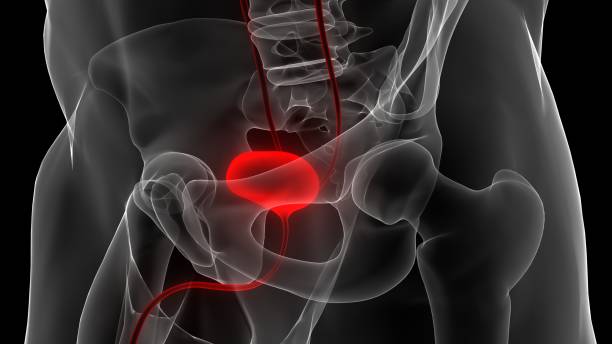

방광암은 방광 내부에 악성 종양이 생긴 것을 말합니다. 이 종양은 방광 벽에서 시작하여 방광 내부로 침입할 수 있으며, 심각한 경우 다른 조직이나 기관에도 전이될 수 있습니다.

방광암이 발생하면 방광 내부에 있는 세포들이 비정상적으로 증식하면서 방광의 용량이 줄어들게 됩니다. 이로 인해 환자는 짧은 시간 간격으로 소변을 자주 내게 됩니다.

방광암이 발생하면 방광 벽면이 손상될 수 있습니다. 이로 인해 소변을 보거나 방광이 가득 찰 때 통증을 느낄 수 있습니다.

방광암 환자는 소변이 홍색 또는 갈색빛을 띌 수 있습니다. 이는 방광 내부 세포의 이상 증식으로 인해 생길 수 있는 출혈의 결과입니다.

환자는 소변에 피가 섞일 수 있습니다. 이는 방광암으로 인해 생길 수 있는 출혈의 결과입니다.

방광 벽면이 두꺼워지면 방광이 축소되는데, 이로 인해 방광암 환자는 방광을 완전히 비우지 못하고, 소변이 조금 남게 될 수 있습니다.

방광암이 진행되면 방광 근육이 약해지면서 소변을 배출하는데 어려움을 느낄 수 있습니다.